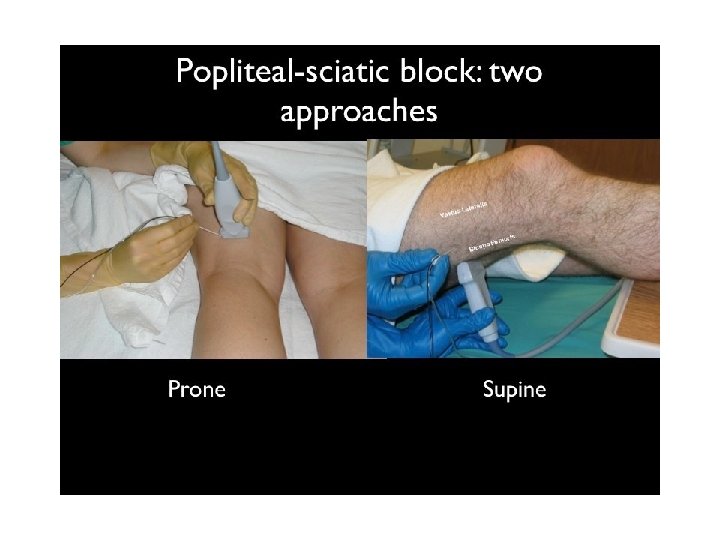

Popliteal Sciatic Block • Anesthetizes the entire leg below the tibial plateau except the skin of the medial aspect of the calf and foot (saphenous nerve distribution) • The popliteal block is performed on the sciatic nerve proximal to this bifurcation; about 10 cm from the popliteal crease. • Landmarks include the popliteal crease, tendons of the biceps femoris and the semitendonisimus muscles • Used for minor surgeries of the distal lower leg, foot or ankle

Popliteal Sciatic Block • Pt. is positioned in the prone position or in a modified exaggerated lateral position with the leg to be blocked uppermost and flexed at the knee touching the bed and the underlying leg straight. • Advantages are improved calf tourniquet tolerance and an immobile foot. • Complications may be persistent foot drop with potential pressure necrosis